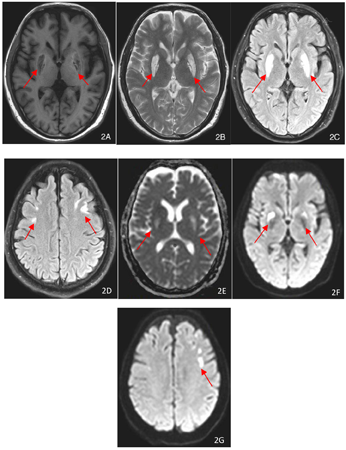

外院相关检查:2022年7月14日血气:pH 7.17,二氧化碳分压(PaCO2)21 mmHg,氧分压(PaO2)159 mmHg,钠133 mmol/L,葡萄糖6.8 mmol/L,乳酸17 mmol/L,实际碳酸氢根7.7 mmol/L,标准碳酸氢根10.1 mmol/L。肾功能:肌酐1107 μmol/L,尿素氮20.2 mmol/L。2022年7月14日头颅CT:两侧基底节区对称性密度减低。2022年7月19日头颅MR+增强:双侧额叶及基底节见斑片状,小片状稍长T1稍长T2信号影,增强强化不明显,弥散像呈高信号,ADC呈低信号,周围可见水肿信号,考虑代谢性脑病,结合临床考虑肾性脑病可能。入住我院相关化验,2022年7月31日血气分析,pH 7.45,二氧化碳分压31.1 mmHg,氧分压149.8 mmHg,实际碳酸氢根21.4 mmol/L,标准碳酸氢根22.7 mmol/L,阴离子间隙20.5,乳酸0.6 mmol/L,钾3.84 mmol/L,钠138.5 mmol/L,钙1.23 mmol/L。2022年7月31日血常规:白细胞9.3×109/L,中性粒细胞占比0.787,红细胞计数2.58×1012/L,血红蛋白83 g/L,血小板计数230×109/L,2022年8月1日生化:白蛋白34 g/L,总胆红素3.9 μmol/L,谷丙转氨酶3 U/L,尿素氮35.48 mmol/L,肌酐645 μmol/L,尿酸488 μmol/L。尿常规:尿蛋白阳性1+,尿隐血阳性3+,红细胞计数131/μl;甲状旁腺激素214.9 pg/ml。2022年8月5日腹透液常规:有核细胞计数10×106/L,蛋白定性2+;血钠125.9 mmol/L;2022年8月13日24 h尿钠328.6 mmol/24h,24 h尿量2900 ml。2022年8月15甲状腺功能:FT3 1.36 pg/ml,FT4 0.68 ng/dl。影像学检查:2022年8月2日胸部+腹部CT:两肺下叶微小结节,胆囊结石,胰头周围多发钙化灶,两肾多发囊性灶,左肾小结石。2022年8月2日头颅MR:两侧基底节、额叶异常信号,结合临床考虑尿毒症脑病,两侧额部硬膜下积液,两侧乳突炎,两侧上颌窦囊肿。2022年8月23日头颅MR:两侧基底节、额叶异常信号,符合尿毒症脑病,较前(2022年8月2日)吸收。发病第20天头颅MRI及CT表现见图1,发病第41天头颅MRI表现见图2。

豆状核叉征是一种特征性的影像学表现,可视为尿毒症脑病的基底神经型,在CT上表现为双侧豆状核区对称性低密度改变,在头颅MRI上为双侧豆状核区对称性T1WI像低信号,T2WI像及T2FLAIR像高信号,这种高信号尤以豆状核边缘的内囊后肢及外囊最为明显,且两者向后延伸形成叉状外观,叉子的柄由内囊后肢和外囊后部融合而成,内囊后肢和外囊分别构成叉子的内侧臂和外侧臂,内外两臂之间夹着豆状核(包括壳核及内外侧苍白球)[1]。